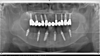

Les cas extrêmes de déchaussement peuvent être réhabilités grâce à des couronnes ou des bridges fixes supportés par des implants et reconstruisant toutes vos dents.

Avant

cas traité17